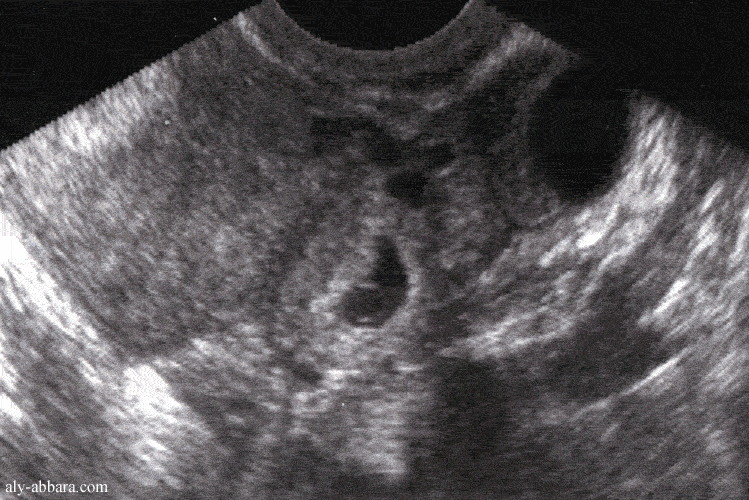

Grossesse extra-uterine tubaire avec l'individualisation du sac gestationnel